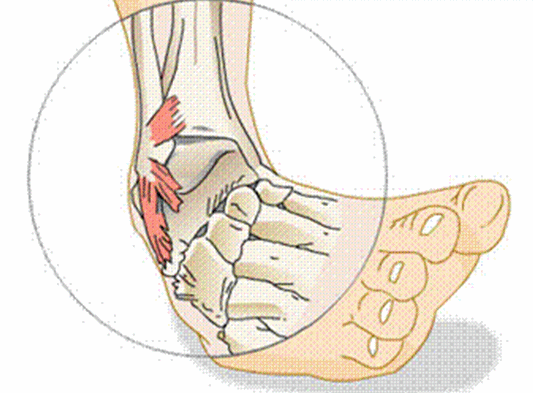

ankle fracture / dislocation mechanism (2)

foot forced inward/outward, foot planted and lower leg forcibly rotated

signs/symptoms of ankle fracture/dislocation

severe pain/deformity, open fracture, no weight bearing

ankle fracture/dislocation treatment

immobilize, apply light pressure, ice + elevate if no open wound